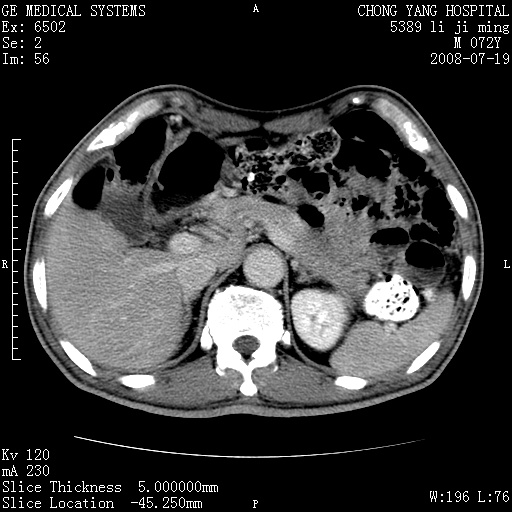

以下是引用zjzjr在2008-7-19 20:57:00的发言:[br]胰头增大,边缘模糊,周围可见渗出影,右侧肾前筋膜增厚.支持胰腺炎.

以下是引用yangyudong333在2008-7-20 6:56:00的发言:[br]胰腺增大尤以胰头明显,边缘模糊,周围可见渗出影,右侧肾前筋膜增厚,肠管於涨.支持胰腺炎

以下是引用不学无术在2008-7-19 23:15:00的发言:[br]胰腺增大尤以胰头明显,边缘模糊,周围可见渗出影,右侧肾前筋膜增厚,肠管於涨.支持胰腺炎